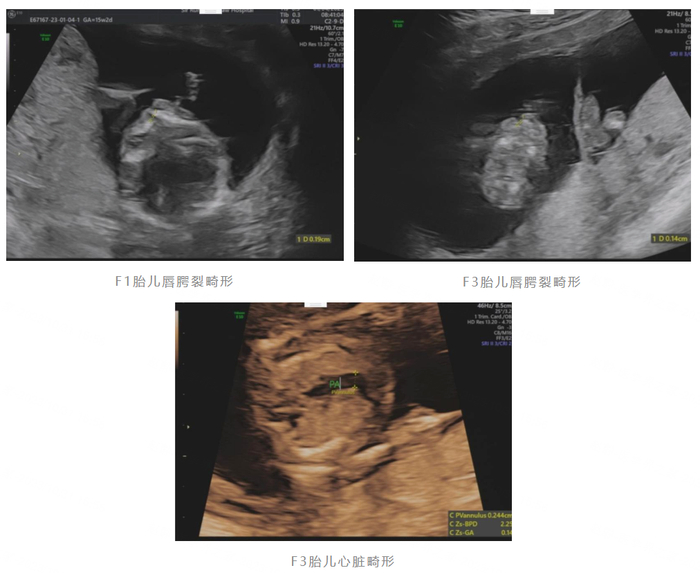

谁承想,这次减胎前胎儿超声系统检查竟发现了问题:三个胎儿(分别标记为F1、F2、F3)中,F1胎儿的左侧唇部、腭部连续性中断,提示唇腭裂畸形;F3胎儿左侧唇部、腭部连续性中断,提示唇腭裂畸形,左右心室比例异常,肺主比异常。也就是说三个宝宝中,有两个宝宝是异常的

其中,F1胎儿是独立的绒毛膜囊羊膜囊,但F2与F3是一个胚胎一分为二的两个胎儿。面对这一晴天霹雳,小王夫妇顿时六神无主——F2和F3位于同一个绒毛膜内,一卵双胎,该如何保证那唯一一个健康宝宝(F2)的安全?

又熬过两周,陆主任再次为小王安排了胎儿超声复查,结果仍显示,F2未见明显异常,F3胎儿多发畸形:胎儿双侧唇腭裂;胎儿室间隔缺损,单一大动脉,考虑永存动脉干畸形。尽管内心忐忑,但为了健康宝宝的安全,避免存在严重先天缺陷的宝宝来到人世间受苦,也基于对陆主任团队专业性的足够信任,小王还是坚定地预约了第二次减胎手术。陆主任团队在进行了充分的术前讨论、准备及手术知情同意后,最终成功完成了射频消融减胎术。小王在短暂的住院保胎和预防感染后顺利出院。